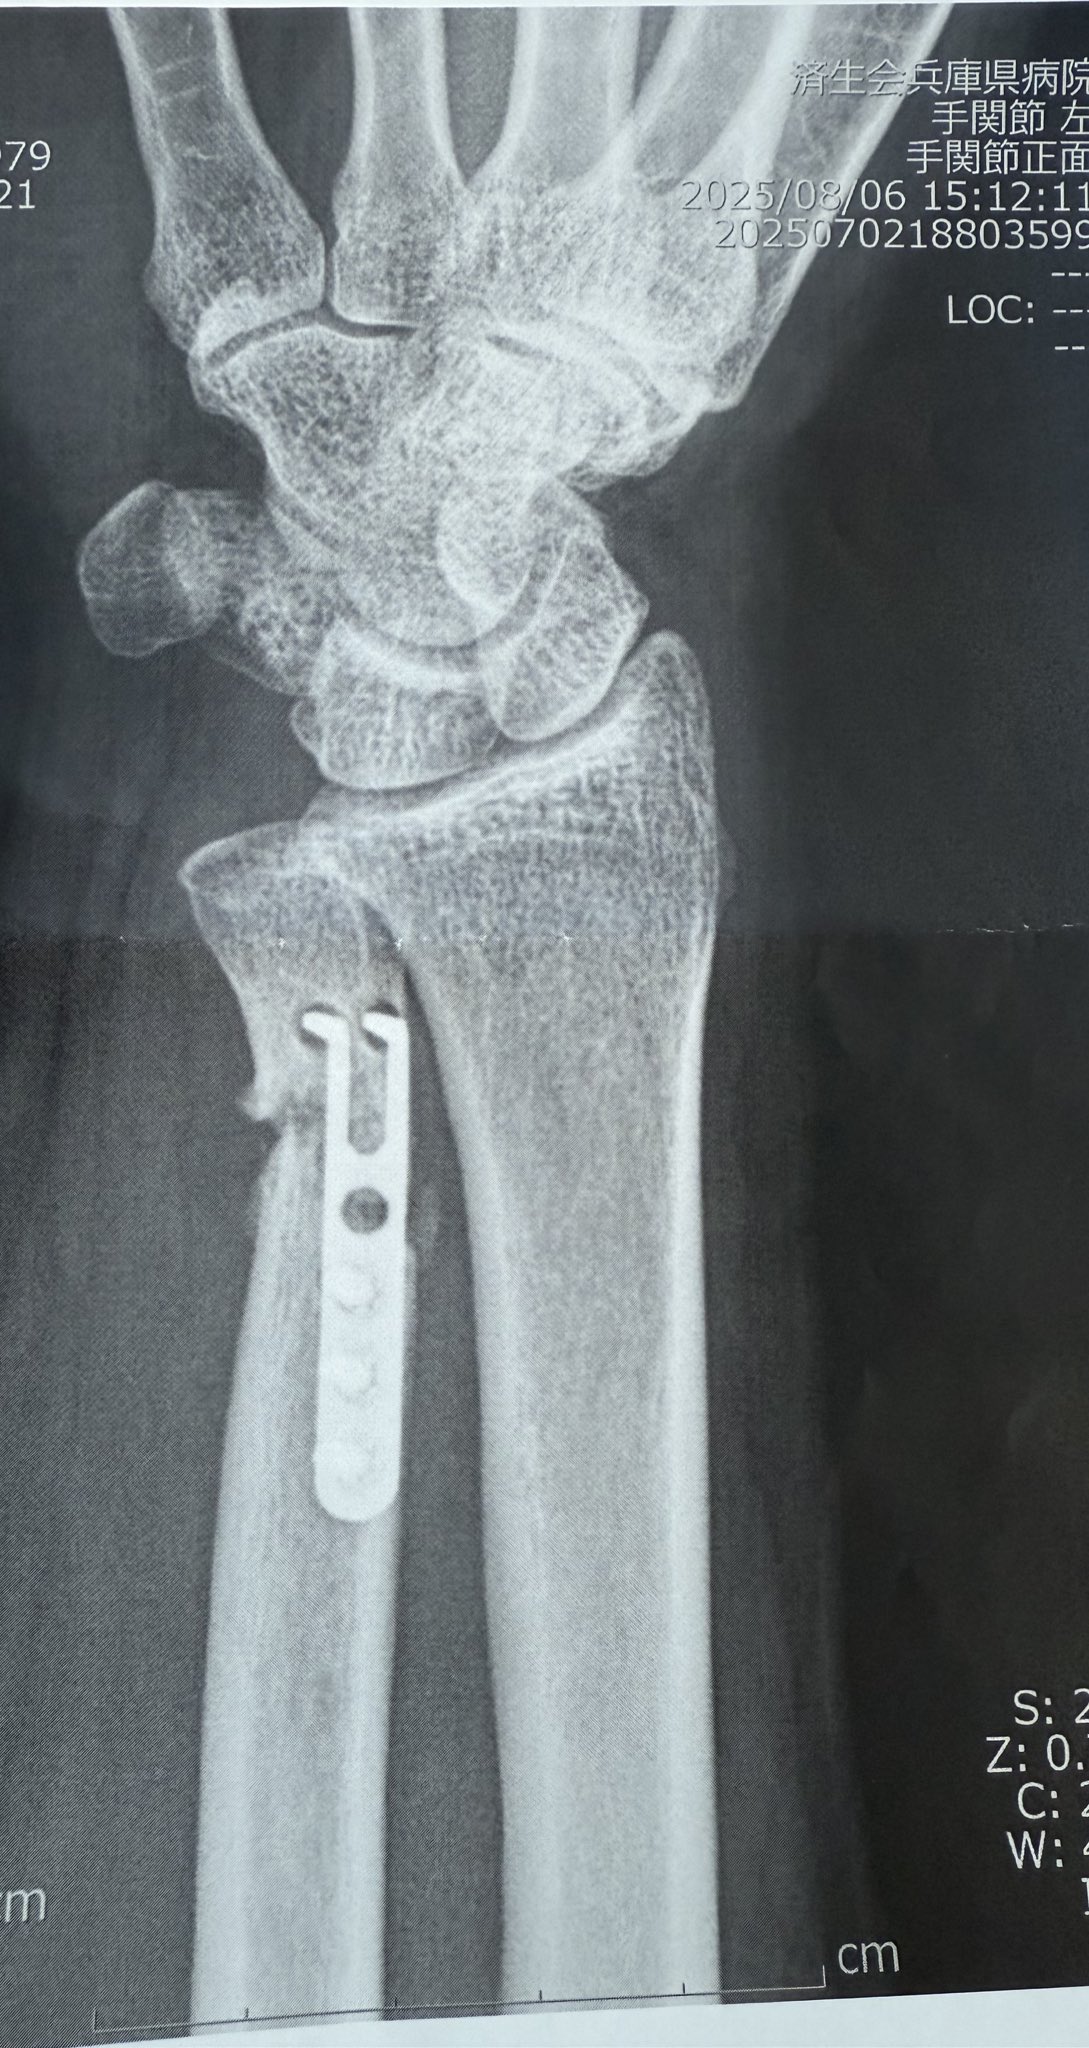

TFCC損傷尺骨突き上げ症候群druj不安定症入院手術尺骨短縮術ギプス手術跡レントゲン入院記録抜釘手術。

tfcc損傷と尺骨短縮術後㊻抜釘後その3ホンダのTFCC損傷と更年期主婦のブログ。

TFCC損傷・尺骨短縮術 入院~手術~術漁師の徒然なるブログ。